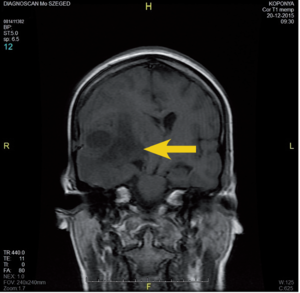

3.6.2. Daganatok: az agy (64–72. ábra)

- MRI: T2, FLAIR, T1/T1gad, DWI.

- CT: natív és kontrasztos – akut eset, staging, mész kimutatására.